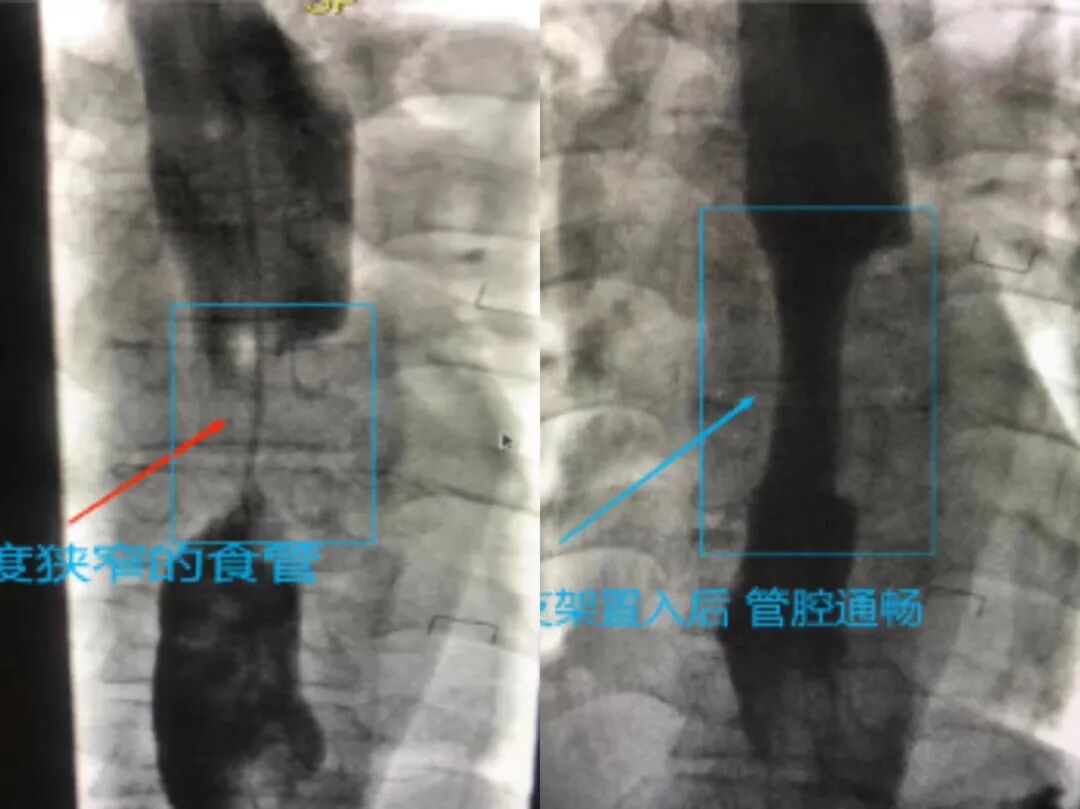

(我院某患者因食管癌进食困难,行食管支架置入术后恢复饮食功能)

结合我院目前的具体情况,DSA导管室和内、外、肿瘤等多科室协同合作,进行了外周介入多项手术,自2019年至今在上级医院的帮助下开展约200余台手术,填补了我院多项空白并致力于新技术的拓展,如肝癌、肺癌等恶性肿瘤的精准栓塞、治疗;咳血患者的支气管肺动脉栓塞术;食管癌患者扩张、支架置入;鼻肠引流管置入;下腔静脉滤器的置入、取出等等,在疾病的预防、控制及治疗的上均取得了良好的效果。